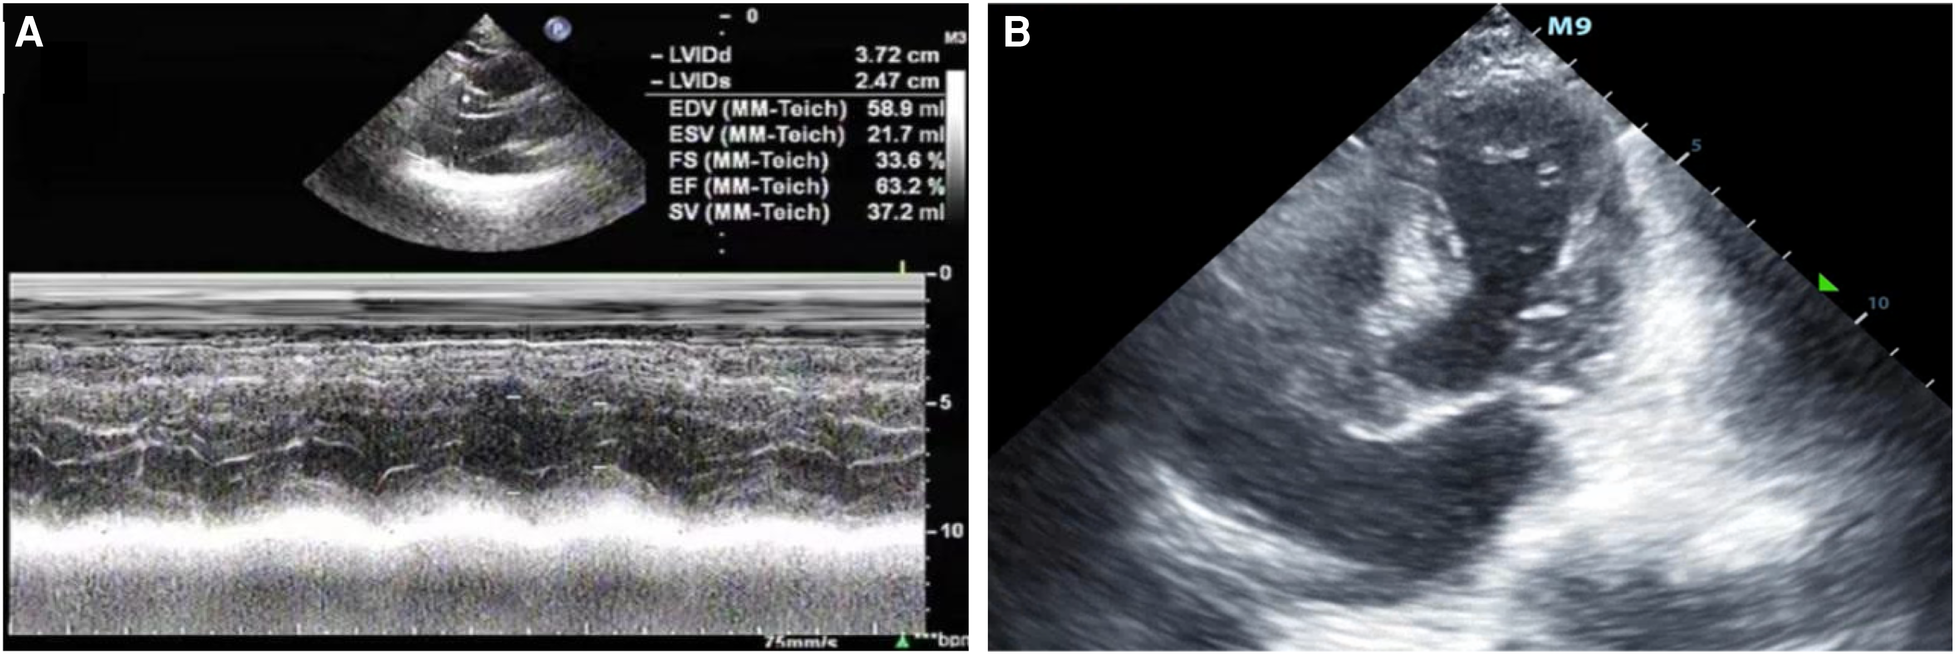

A 67-year-old male patient was admitted to our respiratory department on January 8, 2024, with the chief complaint of a “recurrent cough with sputum for over six years, aggravated for more than one month”. The admission echocardiogram (Figure 1A) and electrocardiogram (Figure 2) showed no significant abnormalities in cardiac structure and function. High-sensitivity troponin I was measured at 0.012 ng/ml (normal range: 0–0.0535 ng/ml), and BNP was 187.1 pg/ml (normal range: 0–125 pg/ml). The patient had a history of chronic obstructive pulmonary disease for over six years, no history of allergies, and no other significant medical history.

Figure 1

(A) The patient was admitted to the hospital with a left ventricular ejection fraction of 63.2% and normal systolic and diastolic function. (B) After admission to the ICU, bedside color ultrasound examination of the heart showed that the apex of the heart was round and blunt, with left ventricular systolic dysfunction and basal ganglia contraction.

After being admitted to the ICU, the patient quickly developed purpura on both lower limbs, causing the whole body feeling cold and clammy. At this time, the patient's vital signs were as follows: temperature of 36 degrees Celsius, heart rate of 152 beats per minute, blood pressure of 75/46 mmHg, respiratory rate of 35 breaths per minute, and oxygen saturation of 96%. We immediately administered epinephrine to maintain blood pressure, along with milrinone for cardiac support, and used a ventilator to assist the patient's breathing. Bedside echocardiography indicated the patient's left ventricular ejection fraction (EF) was 30%–40%, with segmental dysfunction of the left ventricle and a rounded apex, suggesting the possibility of stress-induced cardiomyopathy (Figure 1B). Chest CT indicated bronchospasm without clear signs of infection (Figure 3). Emergency blood tests showed high-sensitivity troponin I at 3.24 ng/ml and BNP at 4850.2 pg/ml. The electrocardiogram showed extreme clockwise rotation, left atrial abnormality, abnormal Q waves in leads I and aVL, poor progression of R waves from leads V1 to V6, ST segment elevation of 0.05–0.15 mV in leads V3–V6, and T-wave changes (Figure 4). After a consultation with the cardiology team, emergency percutaneous coronary intervention (PCI) was recommended.